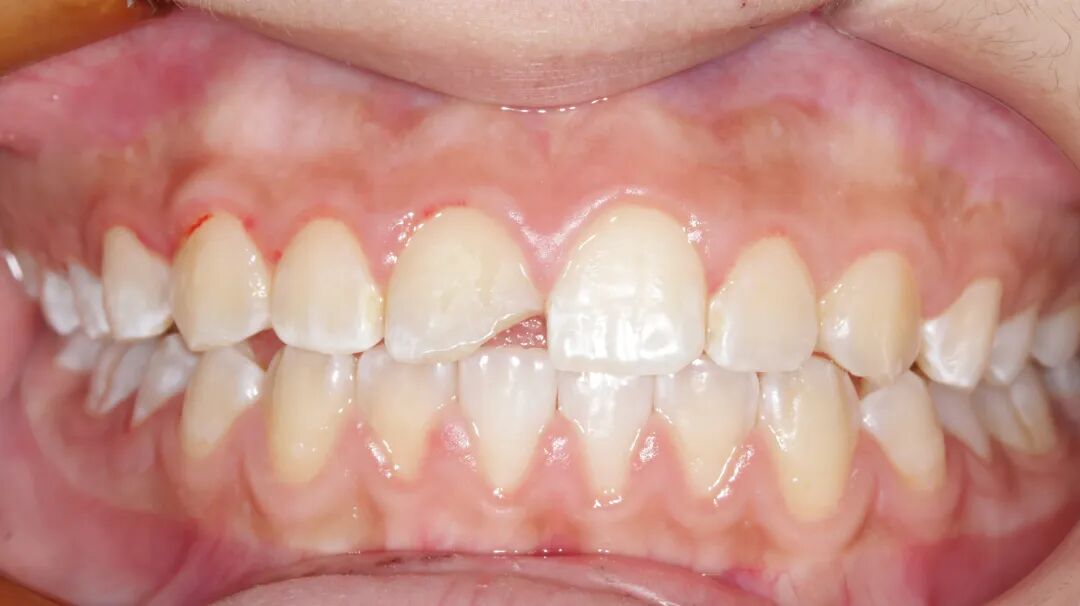

上颌中切牙瓷贴面美学修复

性别:女     年龄21岁

主诉:前牙氟斑牙影响美观

现病史:病人因从小有高氟地区生活史,导致全口氟斑牙,现因前牙区氟斑牙呈黄褐色影响美观,要求处理

既往史:既往体健,否认疾病史及药物过敏史

检查:牙龈无红肿,口内卫生良好

治疗方案:铸瓷贴面美学修复